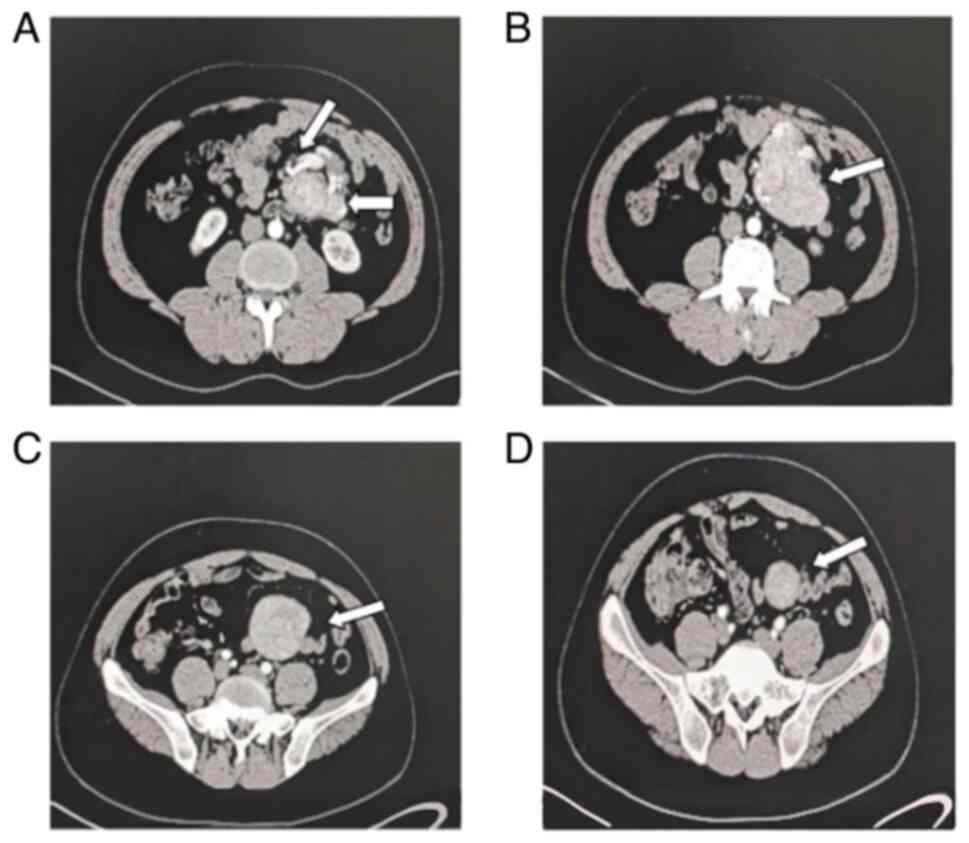

The laboratory results, including blood routine, liver function, kidney function, electrolytes, tumor markers, urine routine and stool routine tests, were all within the normal parameters. HIV test was negative. The chest X-ray was normal. Computerized tomography (CT) scan revealed a well-defined soft tissue density lesion measuring 16x12x10 cm, encircling large mesenteric blood vessels within the left mid-abdominal cavity (Fig. 1). Although CT scan revealed a clear soft tissue mass with calcification inside the mesentery, suggestive of Angiosarcoma, differential diagnoses including Castleman's disease and lymphoma could not be definitively excluded. At this point, fine needle aspiration was considered as a viable option for further pathological clarification; however, the patient declined this procedure. Given the suspicion of a malignant tumor, surgical intervention was chosen to facilitate a definitive diagnosis and subsequent treatment.

Figure 1

Relationship between tumors and mesenteric vessels (arrows indicate mesenteric vessels). (A) Enhanced computed tomography shows that the huge mass originates from the starting point of the mesenteric vessels, arterial enhancement of the mass, and feeding vessel. (B) The mass is surrounded by large mesenteric blood vessels and the boundary is unclear. (C) Relatively isolated location of mass. (D) The lowest boundary of the mass.